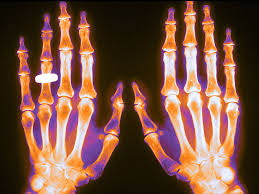

- Reumatología

- Traumatología